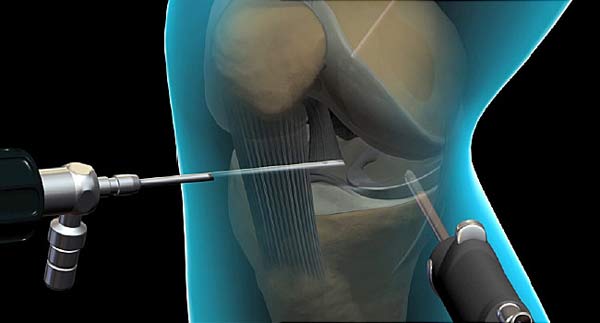

A diagnostic knee arthroscopy is a procedure to look inside your knee joint. An arthroscope is a flexible tube with a light and camera on the end. Diagnostic arthroscopy is usually done to check for disease or damage inside your knee.

Anterior Cruciate Ligament Reconstruction or simply ACL Reconstruction is a surgical procedure where the torn ACL ligament is removed and replaced with a graft sourced from the same patient. Usually, the grafts are sourced from the same patient’s hamstring tendon. The surgery is done using minimally invasive arthroscopic techniques. People with the injury to the anterior cruciate ligament get ACL reconstruction surgery.

ACL Reconstruction Surgery Procedures- The patient is administered anesthesia and then taken to surgical theatre.- Slightly below the knee a small incision is made. The incision is made to harvest the graft needed from the hamstring. The semitendinosus and gracilis tendons are harvested through this incision. The incision is usually just 1 inch in length.- The harvested graft is prepared separately. Usually the tendon so harvested is folded and sutured and made into one solid string. The preparation of the graft happens side-by-side as the orthopedic surgeon prepares the knee to take in the graft.

- The surgeon then proceeds to drill two tiny holes on either side of the patella. This incision is required to remove the torn ACL and also to drill tiny hole on the thigh bones that will attach the graft.

- The surgeon then removes the torn ACL from the site. This removal clears the way to place the graft accurately inside the femoral and tibial tunnel.

- Femoral and tibial tunnels are small drills of appropriate depth that are created on the femur (thigh bone) and the tibia (shin bone) by the ortho surgeon. These two drills are required to place the grafts firmly in place.

- The prepared hamstring graft is then pulled inside the intended position and one end of it is placed inside the femoral tunnel and the other end is placed inside the tibial tunnel.

- Bioabsorbable screws are then used to tighten the graft to the tibia bone. These screws do not warrant removal as they fuse naturally with the bones eventually offering stability. On the femoral side, the graft is stabilized and fixed with a small suspensory device with a small button made of titanium.